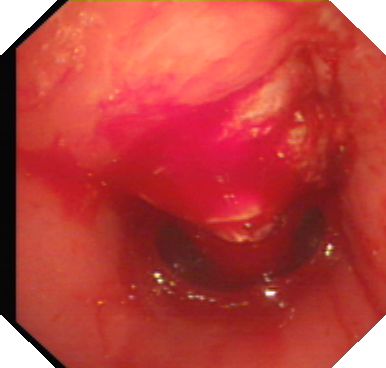

该患者因脑出血后遗症、肺部感染长时间气管切开,随着病情好转准备封闭气切口,反复试封管不成功,行支气管镜检查发现在气切口上端长出一大块肉芽组织阻塞了大部分气管腔,导致了气道狭窄。

(气管内肉芽组织)